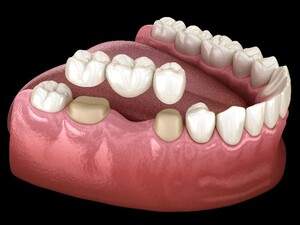

| インプラント | ブリッジ | 入れ歯 | 歯牙移植 | |

| 特徴 | 人工歯根を埋め込み、 その上に被せ物をかぶせる治療。 |

両隣の歯を削り抜歯部位にダミーを置き、 2本の歯で3本の歯の役割をする。 一番後ろの歯には選択できない。 |

両隣もしくは、反対側の歯にバネを掛けて、 人工の歯茎・歯にて補う。 取り外しが必要。 |

抜歯予定の歯に、 親知らずなどの不要な歯を移植する方法。 親知らず・年齢等の条件が必要。 |

| 費用 | 自費診療のみ | 保険診療(金属) 自費診療(セラミック) | 保険診療 自費診療(高精度) | 保険診療可。 しかし、ケースによっては自費になる場合も。 |

| 治療期間 | 3ヶ月〜 | 1〜3ヶ月 | 1〜3ヶ月 | 3〜6ヶ月 |

| 使用感 | 違和感なく使用できる | 違和感なく使用できる | 多少違和感がある | 違和感なく使用できる |

| 周りの歯への影響 | 周りの歯を削らない | 周りの歯を大きく削ってしまう | 周りの歯を少し削る | 周りの歯を削らない |

| 外科手術が必要かどうか | オペは必須 1〜2回行う | 基本的にはないが、 オペが必要な時もある。 |

基本的にはない。 | 抜歯と移植を同時の場合は1回。 同時でない場合は2回行う。 |